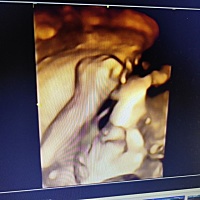

宝宝1个月6天

希望我的宝宝一切顺利